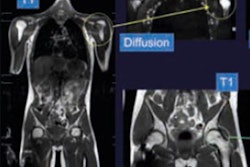

In this study, 57 patients (median age 58, range, 31 to 77) with newly diagnosed, locally advanced, high-grade soft-tissue sarcomas underwent contrast-enhanced baseline MRI scans on a 1.5-tesla system (Magnetom Aera, Siemens Healthineers) prior to treatment and again after two or three cycles of neoadjuvant chemotherapy. In addition, 37 patients underwent a preoperative contrast-enhanced MRI after five or six treatment cycles, which concluded their therapy.

When Crombé and colleagues compared baseline and MRI scans, and abnormalities around the soft-tissue sarcomas, changes in infiltrative growth pattern and stable or increased edema contributed to statistically significant reduction in disease-free survival.